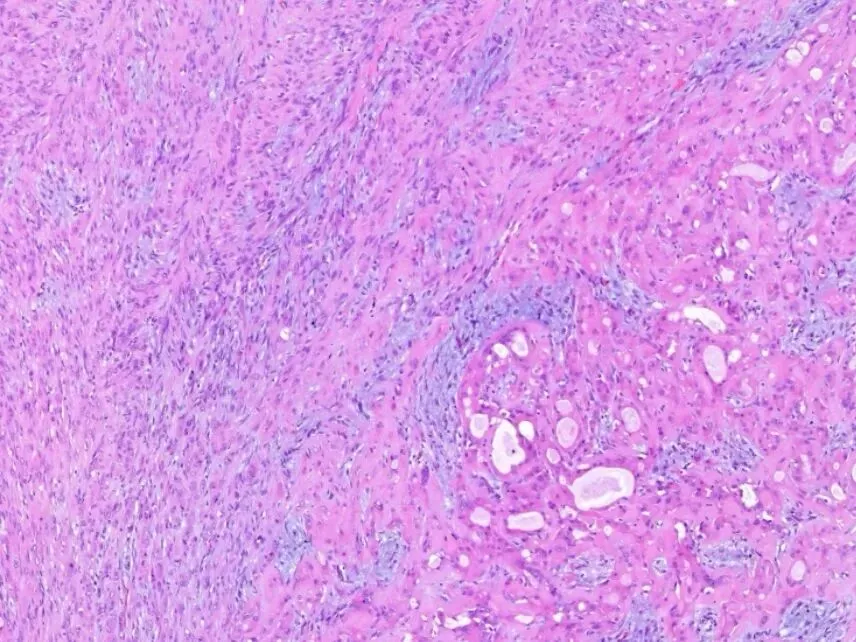

②多形性腺癌:是以细胞形态的一致性、组织结构的多样性、浸润生长方式为特征的上皮性恶性肿瘤。特点为细胞的一致性和结构的多样性。细胞呈圆形或椭圆形,胞质比腺样囊性癌丰富。可见特征性的单列细胞排列或靶环状同心圆样结构。间质纤维组织可见玻璃样变。